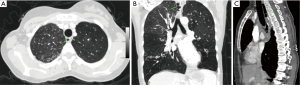

Multidetector computed tomography (MDCT) is the best imaging method to demonstrate tracheal DV. It is useful for evaluating the localization, size, contour, and wall thickness of tracheal DV. Communication between the DV and trachea can also be seen with MDCT. Characteristic MDCT findings of tracheal DV include a thin-walled air sac at the paratracheal area with or without communication to the tracheal lumen (7). MDCT also can be use to distinguish between congenital and acquired lesions, depending on the presence or absence of cartilage and the size of the neck of the DV (5). Slice thicknes of the chest MDCT should be thinner than 1 mm for detailed, accurate evaluation of tracheal DV. Axial, coronal, and sagittal multiplanar images can be obtained with thinner (≤1 mm) slice thicknesses (Figure 1). Connection between DV and the trachea can be evaluated easily with these multiplanar images (Figure 2).